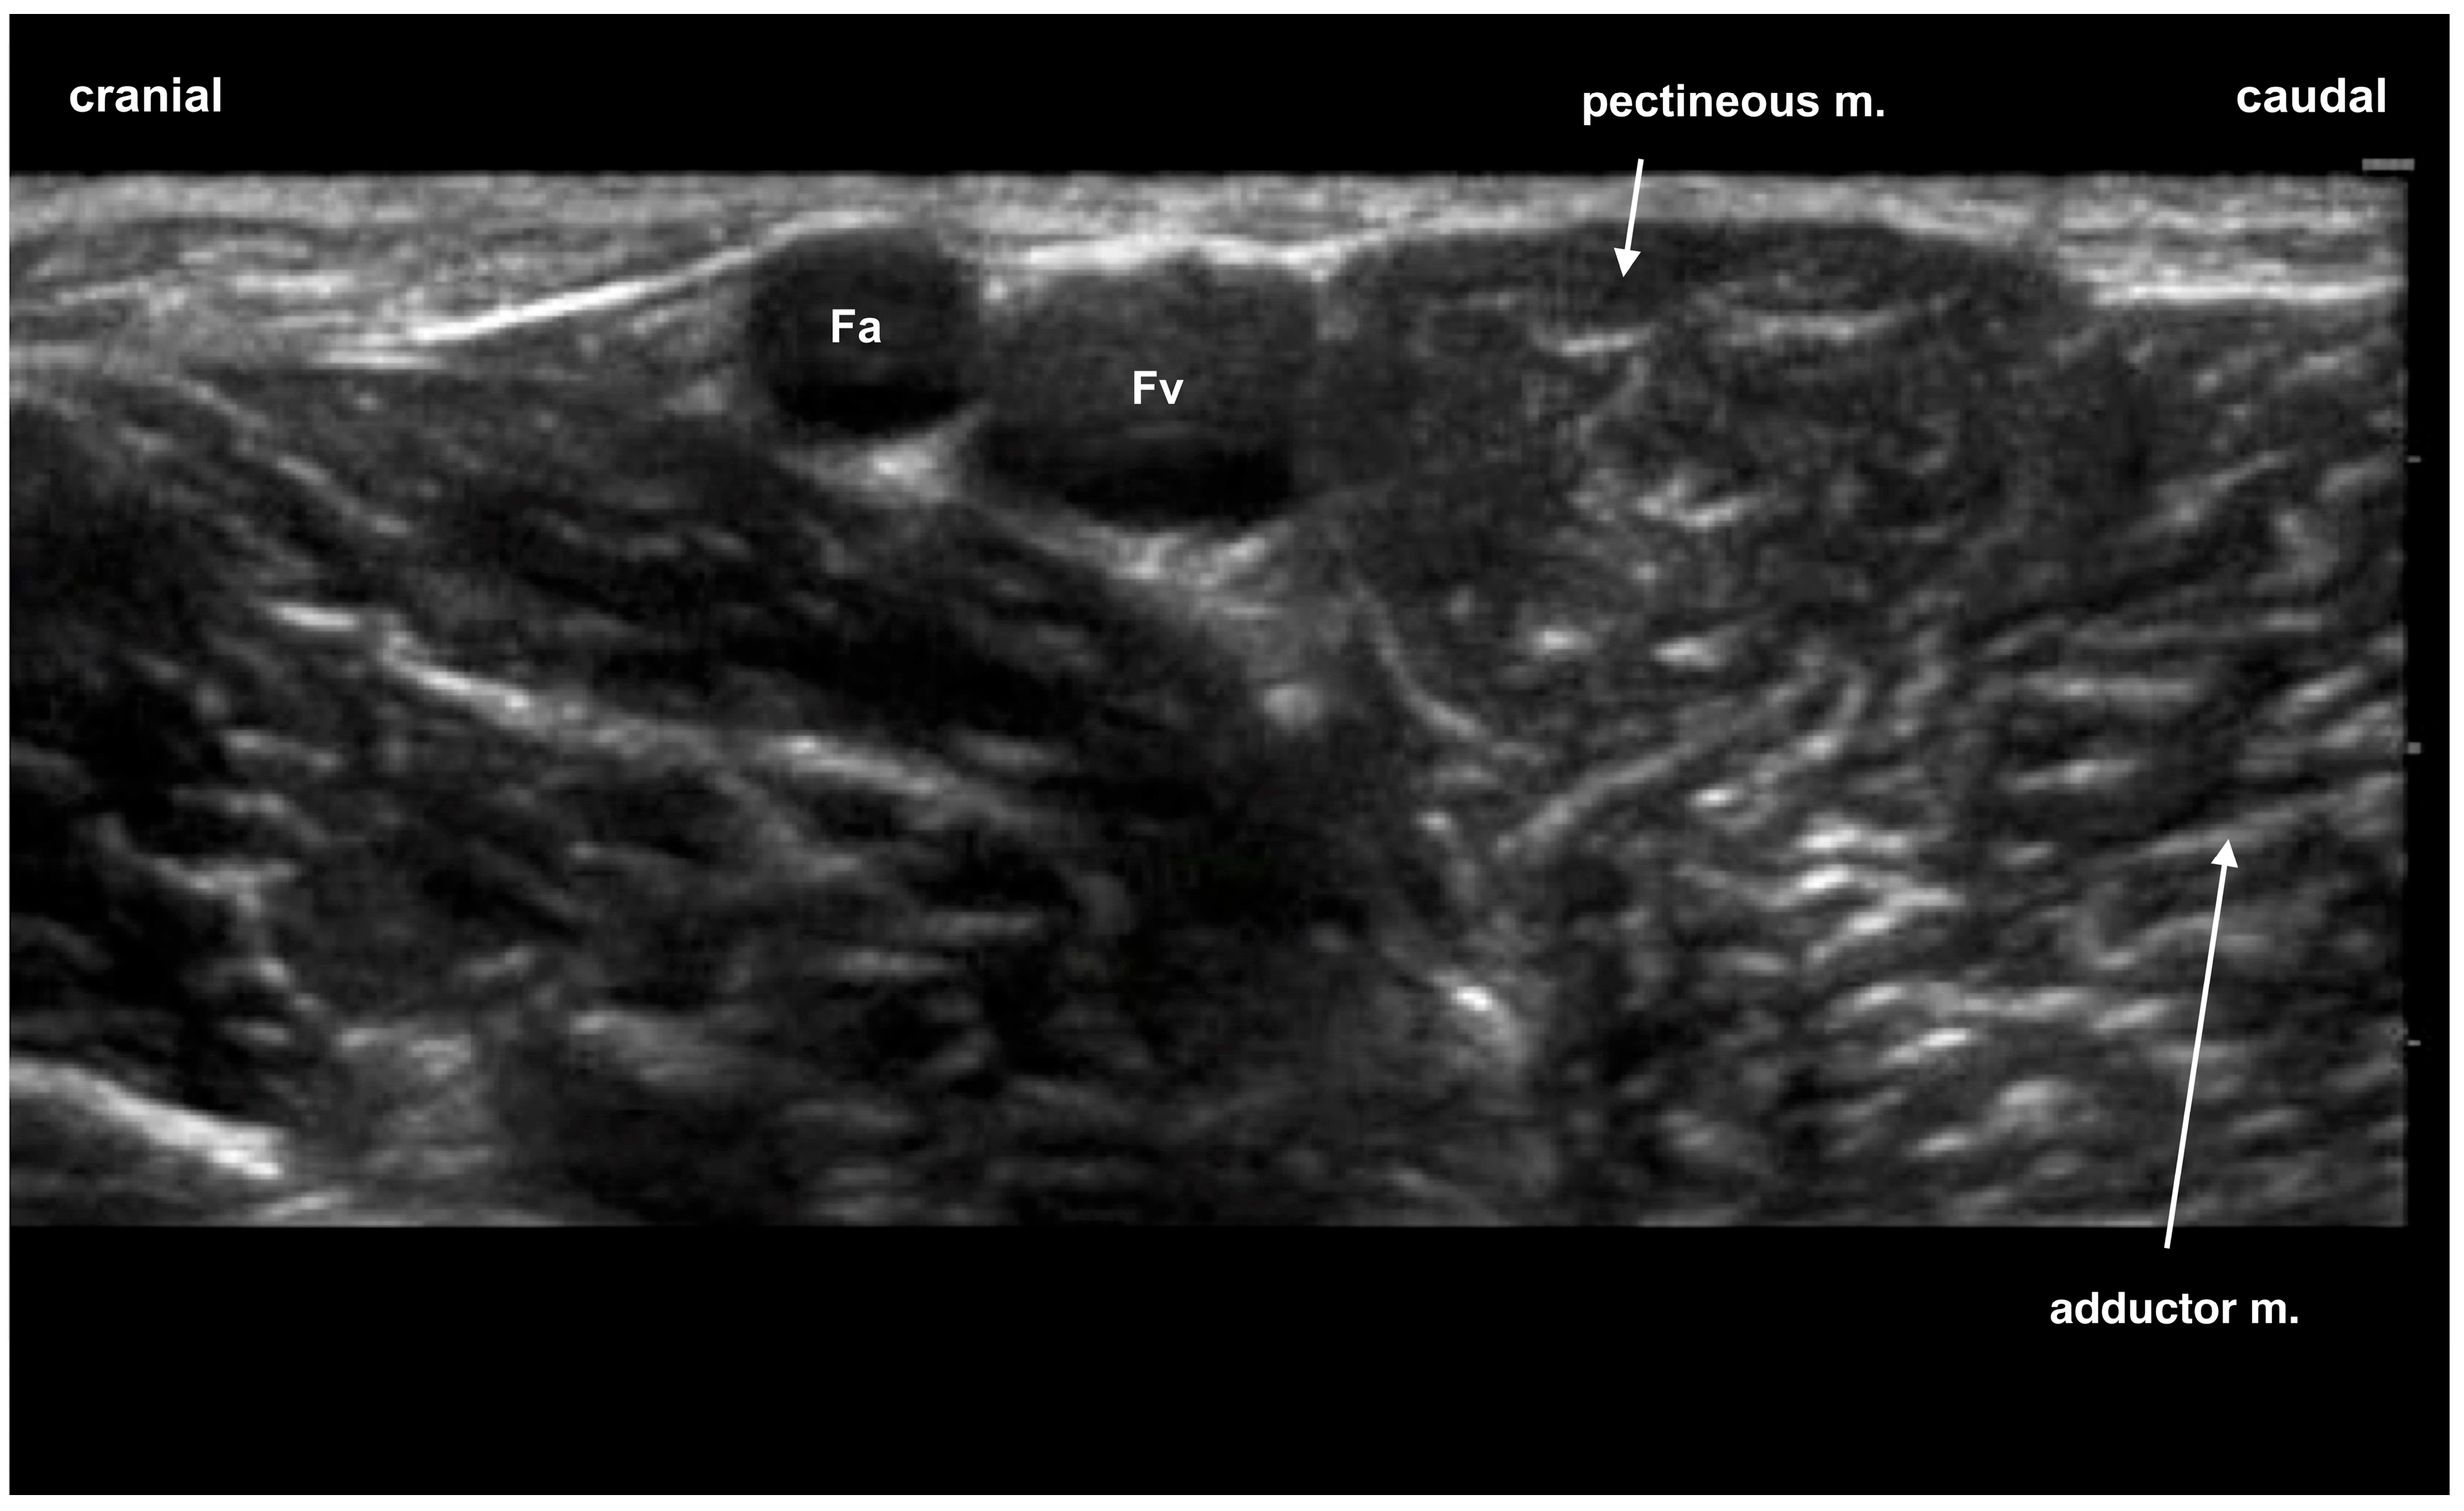

2.1. Phase 1: Anatomical Study

- Castro, D.S.; Garcia-Pereira, F.; Giglio, R.F. Evaluation of the potential efficacy of an ultrasound-guided adductor canal block technique in dog cadavers. Vet. Anaesth. Analg. 2018, 45, 566–574. [Google Scholar] [CrossRef] [PubMed]